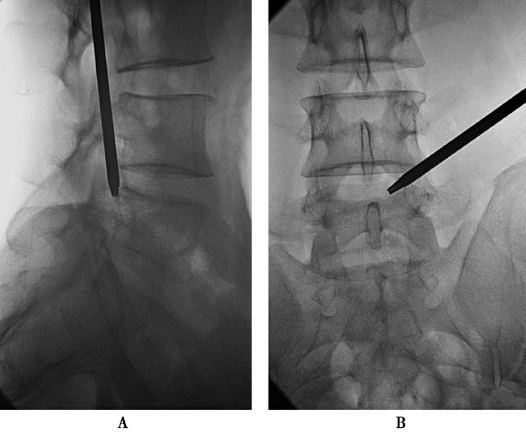

双针技术(图13):调整勺状针的勺状面方向,向脚端、向背侧;在勺状针内,置入笔尖针达突出髓核内。

图13 双针技术A.前后位透视笔尖针针尖达第三靶点;B.侧位透视笔尖针针尖达L5椎体后缘(突出髓核内)。

造影与染色(图14):注入突出物内2ml碘海醇和亚甲蓝的混合液(4∶1)进行造影与染色。

图14造影与染色A.前后位透视;B.侧位透视

1.穿刺时,勺状针头位置受上关节突尖的干扰稍靠头端,要注意出口神经根的保护(图11);应用双针技术是合适的(图13)。

2.造影与染色(图14)笔尖针的位置太靠中线,位靶点边缘,致造影染色欠佳。可退勺状针5mm,笔尖针刺向突出物基底部。